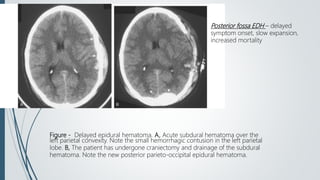

Homogenous hyperdense biconvex epidural

Hematoma in in right temporal convexity.

NECT

• Acute EDH 2/3 hyperdense,1/3 mixed

• Low density swirl sign –active bleeding with

unretracted clot

• Acute EDH with retracted clot = 60-90 HU

Figure - Delayed epidural hematoma. A, Acute subdural hematoma over the

left parietal convexity. Note the small hemorrhagic contusion in the left parietal

lobe. B, The patient has undergone craniectomy and drainage of the subdural

hematoma. Note the new posterior parieto-occipital epidural hematoma.

Posterior fossa EDH – delayed

symptom onset, slow expansion,

increased mortality